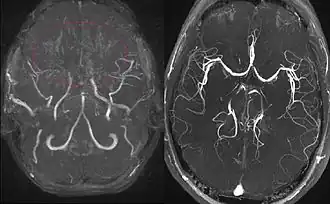

Left: MIP reconstructed MR angiography of a 11-year-old girl with moyamoya disease.

Right: healthy patient, for comparison.

Cerebral angiography is the gold standard of diagnosing moyamoya disease and its progression. According to Suzuki's system, it can be classified into six stages:[12]

Magnetic resonance angiography (MRA) is also useful in diagnosing the disease with good correlation with Suzuki's grading system.[12]